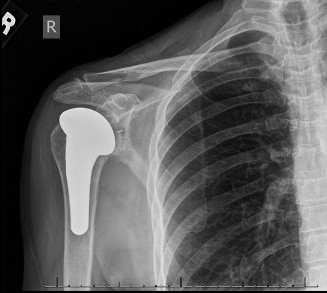

The correct answer is (E). Given that her rotator cuff has atrophied and has fatty infiltration to the point where there are equal parts fat and muscle, this is considered an irreparable rotator cuff tear. Repair should not be attempted because of poor outcomes following repair (see last two paragraphs of this discussion below). A reverse total shoulder arthroplasty is an alternative to repair that should be used in cases of massive, irreparable rotator cuff tears. It is a semi-constrained prosthesis that restores function in patients with massive rotator cuff tears by constraining a concave humeral cap inferior to a semispherical glenoid component (glenosphere). This creates an inferior force-couple and a fulcrum that replaces the stabilizing function of the infraspinatus maintaining a center of rotation around which the shoulder can move. This allows the deltoid to abduct and flex the shoulder without causing the humerus to migrate superiorly and about the acromion. In an elderly patient with a massive, irreparable rotator cuff tear (as in this patient), a reverse total shoulder arthroplasty is the procedure of choice.

It should be noted that reverse total shoulder arthroplasty is also the procedure of choice in patients with cuff-tear arthropathy (aka rotator cuff arthropathy). Characteristics of cuff-tear arthropathy include superior migration of the humerus due to a massive rotator cuff tear, glenohumeral joint destruction, subchondral osteoporosis, and humeral head collapse (see Fig. 2–17). A reverse total shoulder

arthroplasty in this case serves the purpose of eliminating pain caused by glenohumeral joint arthritis while restoring functional motion and is the procedure of choice in patients with cuff-tear arthropathy.

Figure 2–17_X-rays of a patient showing evidence of cuff tear arthropathy. The humerus is migrated superiorly, the glenohumeral joint is destroyed, there is subchondral osteoporosis, and the humeral head is collapsed. (From Ecklund KJ, Lee TQ, Tibone J, Gupta R. Rotator cuff tear arthropathy. _J Am Acad Orthop Surg. 2007;15(6):340–349.)

A hemiarthroplasty (Answer A) was previously the procedure of choice for cuff-tear arthropathy until the reverse total shoulder prosthesis was developed. A hemiarthroplasty reliably relieves pain, but it does not restore function as well as the reverse total shoulder. Also, if the patient had a previous coracoacromial ligament release or anterior deltoid detachment, they are at risk for anterosuperior escape of the humeral head after hemiarthroplasty.

A total shoulder arthroplasty (Answer B) is contraindicated in the case of cuff-tear arthropathy because of glenoid component loosening. If a glenoid component is used in this patient, the superior translation of the humeral head component on the glenoid component could cause it to loosen and rock, producing a “rocking-horse” glenoid component.